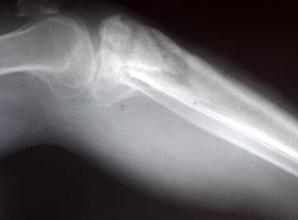

2、急性骨髓炎的症状多在胫骨上端、股骨下端,少数在骸骨、肋骨,髓腔感染使腔内压力增高,急性骨髓炎的症状表现患肢剧痛,被动活动时啼哭,幼儿拒动患肢,早期常不能指出具体疼痛部位。

随着炎症发展,病灶区皮温增高,压痛,脓肿穿破皮质可见皮肤水肿、发红,骨膜下脓肿形成后,压痛局限而显著。骨膜下脓肿破沥侵犯软组织,则迅速形成蜂窝织炎,局部红、肿、热、压痛明显,脓肿形成则有波动。